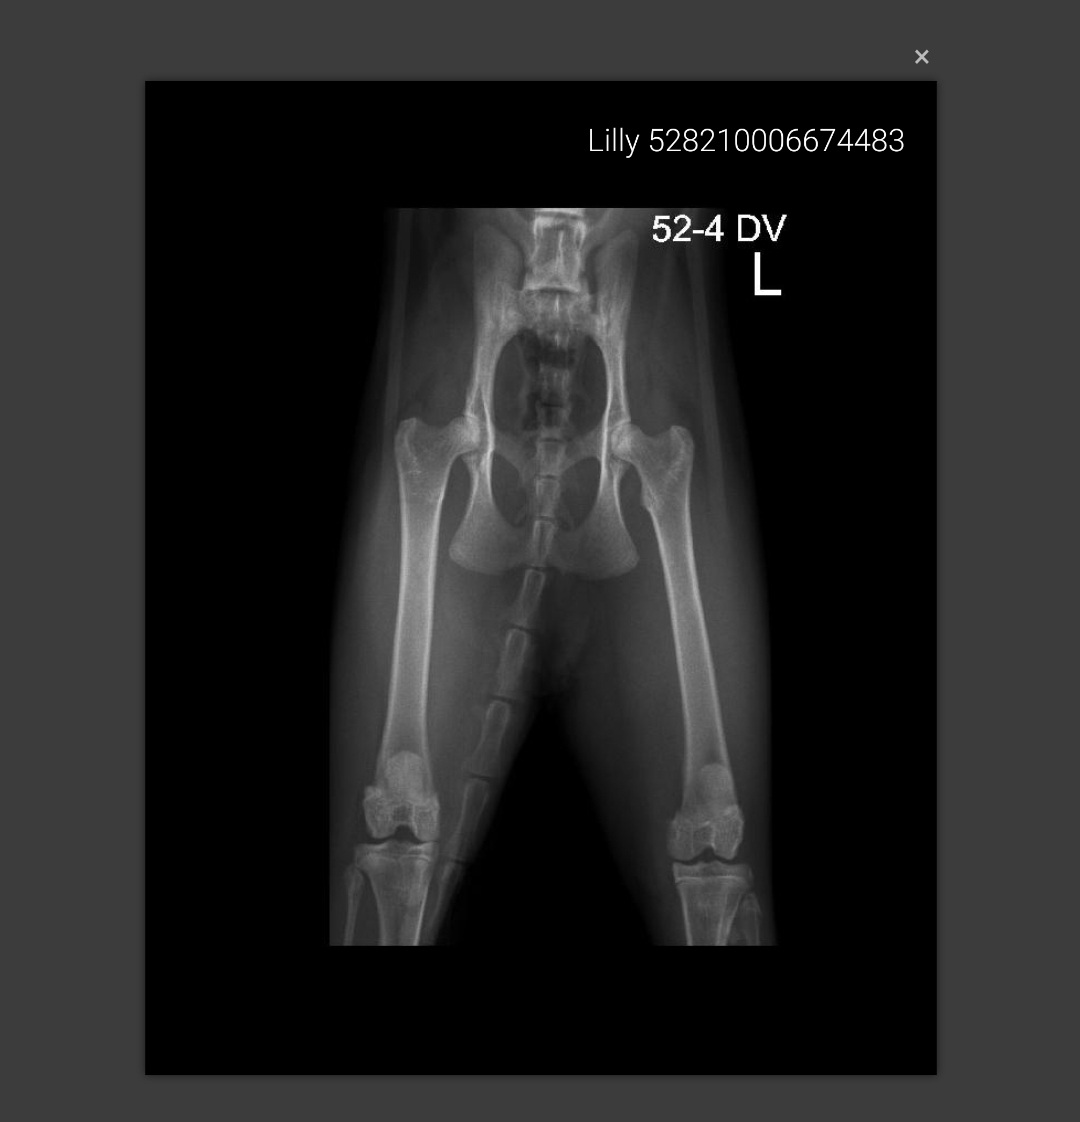

Lily HD gescreend 👌

Afbeelding – 74,7 KB

94 downloads

Download